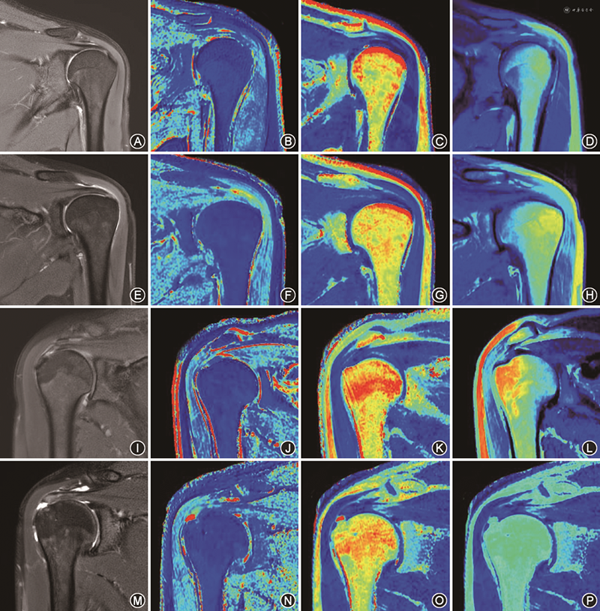

根据纳入及排除标准将对照组志愿者规定为Ⅰ级[9],定义为无肩袖病理症状,MRI图像中冈上肌肌腱形态正常且连续,每个序列均显示均匀一致低信号。根据肩关节镜结果及Zlatkin分级标准,将病例组分为3组[10]:Ⅱ级(肌腱病)定义为肩袖挫伤和肌腱充血、水肿甚至纤维化的病理表现,可复性损伤;Ⅲ级(部分撕裂)定义为不完全撕裂损伤且肩袖损伤导致肩袖肌腱纤维的部分撕裂,可发生冈上肌腱的关节表面上或囊的侧面和肌腱内部;Ⅳ级(完全撕裂)定义为肌腱全层断裂,其导致肩峰下滑囊和盂肱关节的贯通损伤,完全撕裂。冈上肌肌腱各损伤分级对应的MRI图像见图2。

肩袖损伤是肩关节疼痛和功能障碍的最常见原因。在肩袖损伤中,冈上肌肌腱是最易损伤的部分[11]。Neer根据肩关节镜结果将肩袖损伤程度分为Ⅲ期:Ⅰ期为肩袖水肿出血期,Ⅱ期肩袖肌腱炎,Ⅲ期肩袖则出现撕裂情况。本研究将冈上肌肌腱分为3个亚区,在国内首次测量SyMRI序列中冈上肌肌腱的T1、T2及PD值,结果发现T2值对冈上肌肌腱损伤分级有较高的诊断效能,尤其外侧亚区及中间亚区的T2值在鉴别完全撕裂与部分撕裂、肌腱病及正常肌腱中有较高的诊断效能,且T2值与冈上肌肌腱损伤的程度分级呈正相关性。